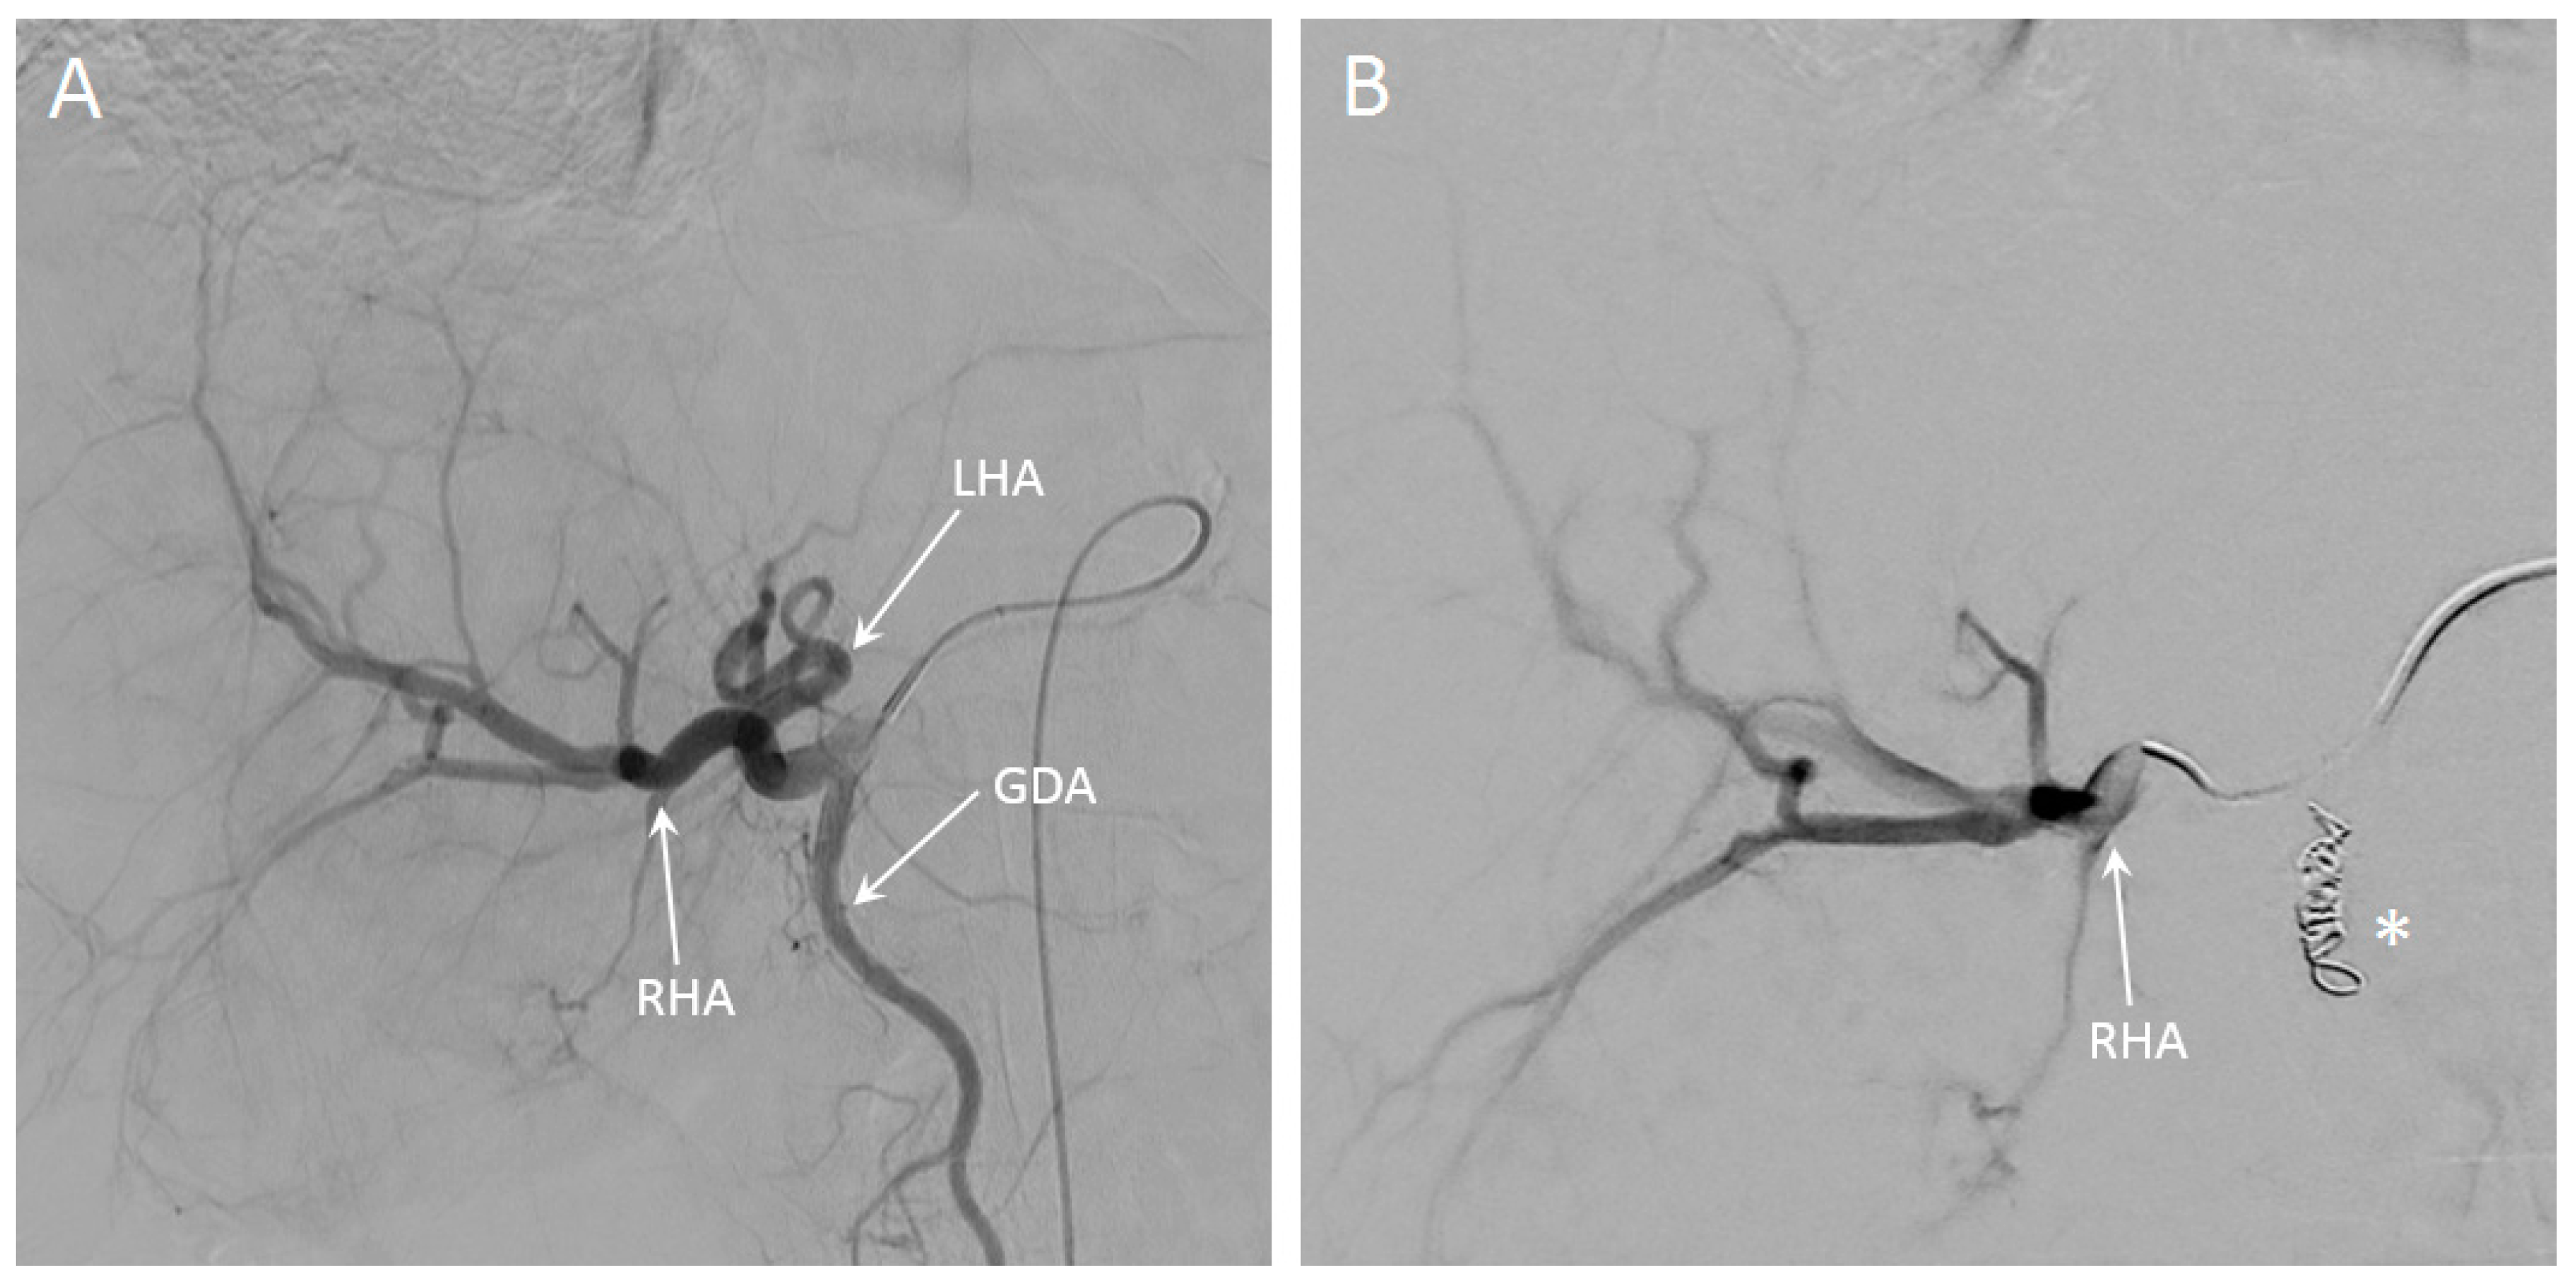

2.2.2. In Vivo Procedure

3.5. In Vivo Visibility during Holmium-166 SIRT

4. Discussion